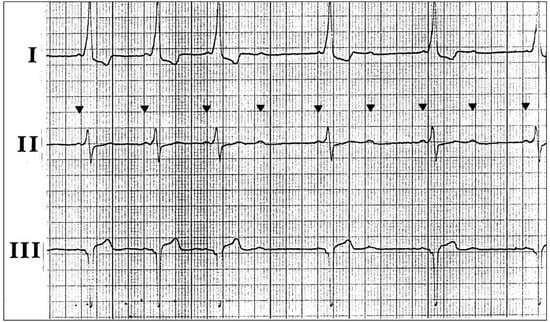

Dyspnoea in a Patient with Alternating Rhythms

1. Case Presentation

2. Questions

- What is your diagnosis?

- What treatment should be proposed?

3. Commentary